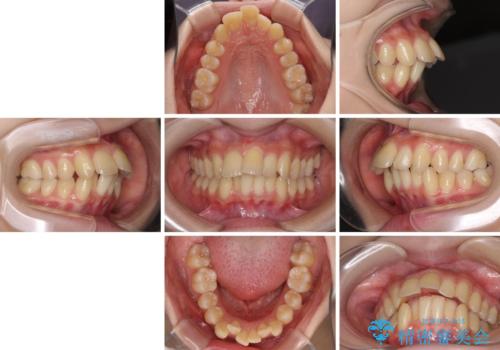

- 上下の出っ歯を気にして来院された患者様です。

口元を積極的に引っ込めるために、上下左右の小臼歯を4本抜歯することとしました。

右上前から2番目の歯が欠損しているため、①矯正治療により欠損部にスペースを作りインプラント補綴を行って前歯を左右対称に揃える、②左右非対称となるが、欠損補綴を行わずに排列する、のいずれかとなりますが、患者様と相談の上②にて矯正治療を行うこととしました。

変則的な歯列であったため、奥歯がしっかりと咬み合うのか、前歯はしっかりと排列できるのかと不安ではありましたが、結果としてはきれいに整った歯列にて終了することができました。